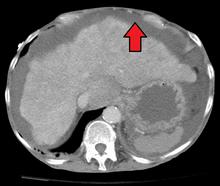

肝硬化腹水

肝硬化腹水的B超影像表现